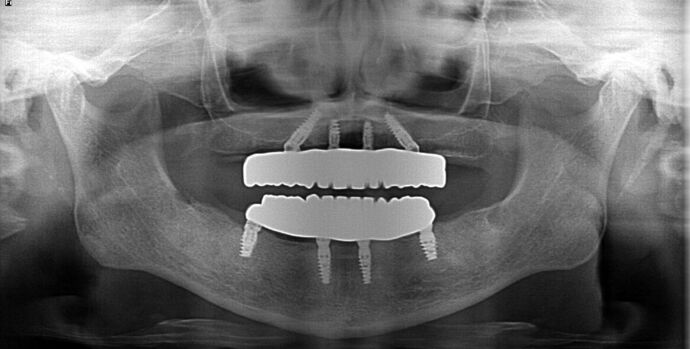

All-on-4/ Full Mouth Dental Implants / Teeth in a Day: Case 20-Gummy smile and failing teeth treatment with Upper and Lower All-on-4 Bridges

This high school teacher was embarrassed about losing her teeth one at a time and had multiple infected teeth causing her pain. She was also unhappy with her gummy smile and found Dr Bidra online. She was informed by 2 other dentists that her gummy smile could not be corrected by dental implants. Dr. Bidra was able to successfully accomplish all her treatment goals by extracting all her teeth and installing Upper and Lower All on 4 implant bridges

Procedures : extractions, gummy smile, new implants, All on 4 , Teeth in a day, no bone grafting and full mouth reconstruction with monolithic zirconia bridges.